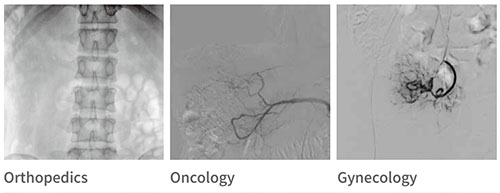

Wide range of clinical applications Multi-departmental surgeries:

Interventional Department:

PLX7100A is widely used in clinical applications and is suitable for interventional operations in various departments.

• Gynecology

• Oncology

• Orthopedics

• Hepatobiliary Surgery

• Intervention/Respiratory

• Gastroenterology